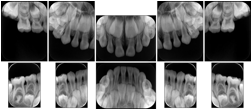

2. A patient requests cosmetic surgery to enhance their facial appearance. The case requires consultation between an orthodontist in New York and an oral surgeon in California. The cephalometric series of 2D projections constructed from the volumetric CT data that is used for the discussion is arranged by a Structured Display for transfer between the two practitioners.

Cephalometric Series Structured Display

Figure OO-2. Cephalometric Series Structured Display